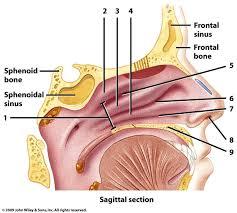

Hard/soft palate

Inferior/middle/superior concha (s.) conchae (pl.)

Nares

Nasal Cavity

Nasal septum

Naso/oro/laryngo-phraynx

Oral Cavity

Paranasal sinuses

Uvula

Vestibule (of nasal cavity)

Vocal folds (=vocal cords)